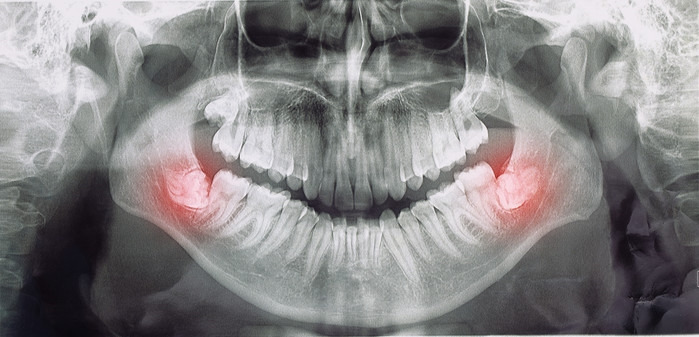

사랑니 발치 후 붓는 이유

사랑니는 일반 치아보다 큰 경우가 많습니다.

게다가 잇몸 깊숙한 곳에 있어요.

큰 치아가 깊숙한 곳에 단단히 박혀있으니,

이런 치아를 뽑아내려면

주변 조직에 자극이 가해질 수밖에 없죠.

부종이 심할 수밖에 없는

매복 사랑니 발치의 경우에서 자주 나타나요.